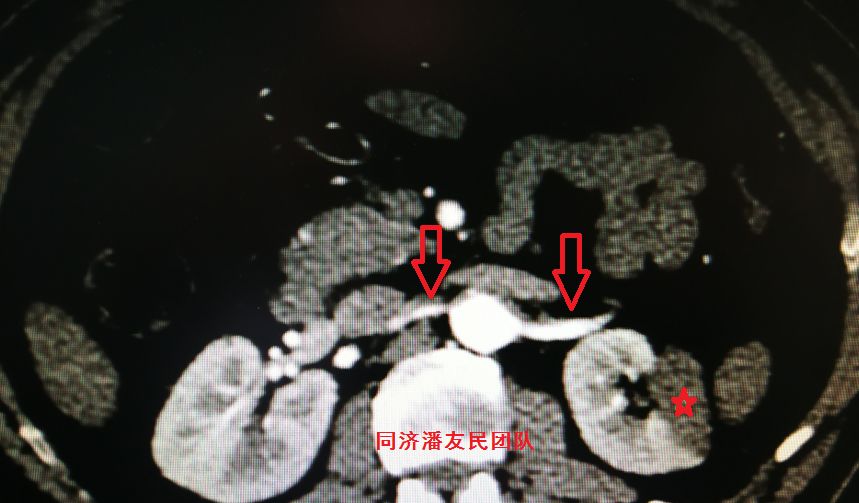

图10:CTA显示肠系膜上动脉由假腔供血(红箭头所示),真腔压闭,左肾及脾脏梗死(红星形所示)

图11:CTA显示双肾动脉由假腔供血(红箭头所示),左肾梗死(红星形所示)